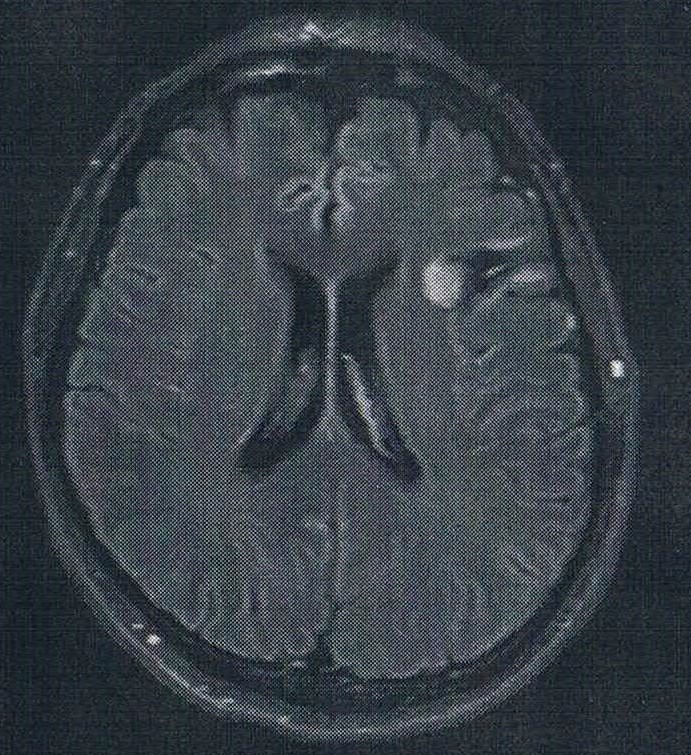

前回、 悪性転化しやすい腫瘍の種類(びまん性星細胞腫グレード2)であるとのことで、1年に一回は造影剤を注射してMRI検査をすることになった。造影剤を使う場合は4時間前から絶食する必要がある。また、撮影前には血液検査が必要でMRI撮影前に済ませる必要がある。今日はたまたま早めに病院に到着していたのと、 採血待ちの順番を飛ばしてもらって何とかMRI撮影に間に合った。血液検査の結果が出るまで45分かかるとのことなので、MRI撮影の1時間前には病院に到着する必要がある。

診断の結果は、特に変化はなく問題なしとのこと。造影剤がしみ込んでいる箇所もないとのことで、悪性度は低い状態を保っている。